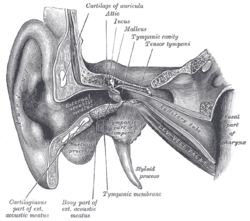

Head and neck of a human embryo eighteen weeks old, with Meckel’s cartilage and hyoid bar exposed. External and middle ear, opened from the front. Right side.

External and middle ear, opened from the front. Right side. Chain of ossicles and their ligaments, seen from the front in a vertical, transverse section of the tympanum.